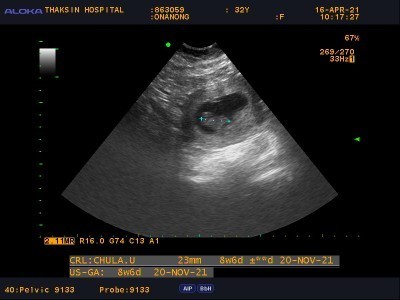

อายุครรภ์8สัปดาห์ ท้องผูกหนักมาก ทานผัก ผลไม้ น้ำเปล่า มากๆ ก็ยังไม่ถ่าย คุณแม่ท่านไหนมีวิธีบ้างค่ะ